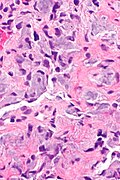

- Spindle cells without atypia and moderate lightly eosinophilic cytoplasm without distinctive cell borders.

- Eosinophilic matrix - described as "gungy" (shabby).[6]

- HPC-like vessels.

- Osteoclast-type giant cells.

- +/-Hemorrhage.

- +/-Calcifications.

- Phosphaturic mesenchymal tumour -- intermed mag.jpg

PMTMCT - intermed. mag. (WC)